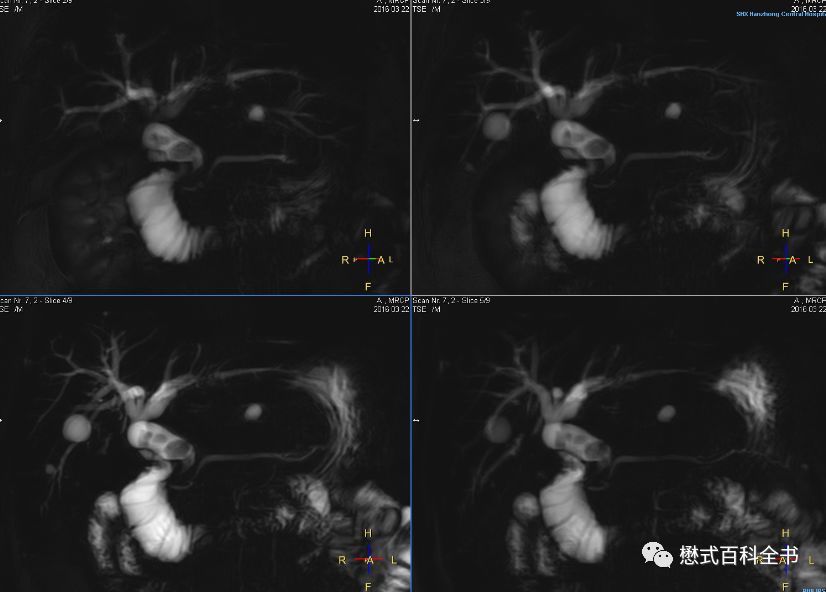

图14~16:扫描MRCP前注射6-542,十二指肠蠕动得到有效抑制,胆总管下段及十二指肠乳头部显示清楚(图片来源于陕西省汉中市中心医院培训)

另外, 一般大部分医院扫描MRCP之前没有做其他处理;也有部分医院扫描MRCP之前,要注射6-542(山莨菪碱)。这样可以抑制胃肠道蠕动,对胆总管下段显示有利。根据我的经验,注射了6-542以后,大概10分钟病人上去检查是最合适的,这个时候差不多病人感觉口干了,药效开始起作用了。